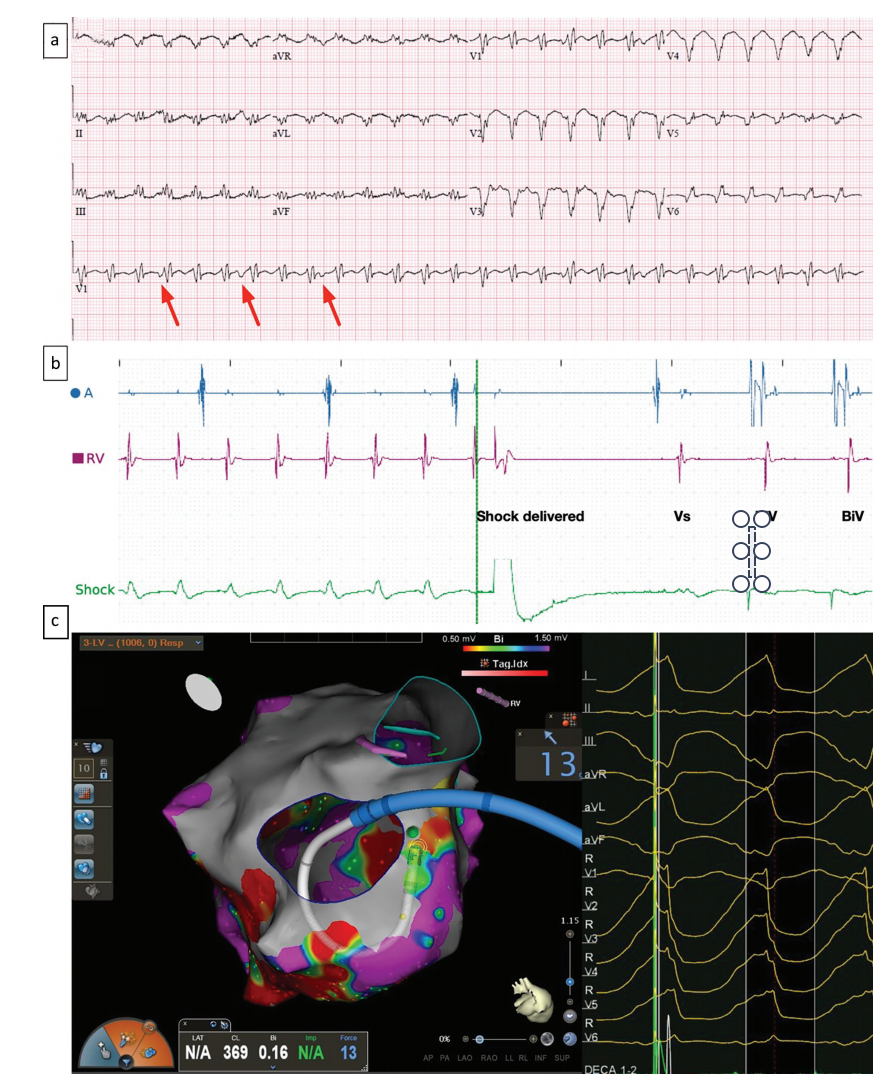

图1,室性心动过速(VT)的心电图诊断。(a) 12 导联心电图(ECG)显示具有右束支传导阻滞结构的宽复律性心动过速。诊断依据是规则的 P 波,P 波与 QRS 波群分离,用红色箭头表示。(b)植入式心脏设备(ICD;本例中为双心室 ICD)的电图。顶线(蓝色)显示心房通道上的近场电信号,中线(洋红色)显示右心室通道上的近场电信号,底线(绿色)显示右心室导联尖端和左锁骨下发生器之间的远场电信号,可将其视为单导联心电图,用作区分传导性心律(即室上性心动过速;SVT)和室性心律的鉴别通道。在面板左侧,RV 通道上的信号多于心房通道上的信号,可见心房通道上的信号与心室通道上的信号分离,这是诊断 VT 的一种模式。设备发出高能量电击(指示)后,VT 终止,出现一次传导性窦性心律搏动(Vs),随后恢复双心室起搏(BiV)。可以看到自发搏动(VS)和双心室起搏(BiV)在鉴别器通道上的形态差异。(c) 因非缺血性心肌病反复冲击而接受 VT 消融术的患者的电生理学研究数据。图像显示导管通过二尖瓣进入左心室。左心室外壳上的颜色表示测量到的双极电压,用来指示组织是否健康,紫色代表电压在正常范围内,红色代表电压严重降低,在病变组织中会出现。面板右侧显示了正在接受治疗的 VT 的 12 导联心电图。该患者通过消融术成功治疗了 VT,并在随访期间(撰写本报告时为 25 个月)未再受到电击。